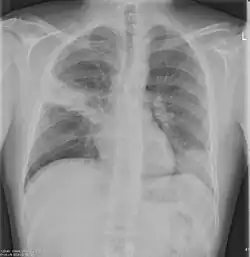

Chest X-rays and X-ray computed tomography (CT) can reveal areas of opacity (seen as white), indicating consolidation.[14] CAP does not always appear on x-rays, sometimes because the disease is in its initial stages or involves a part of the lung not clearly visible on x-ray. In some cases, chest CT can reveal pneumonia not seen on x-rays. However, congestive heart failure or other types of lung damage can mimic CAP on x-ray.[16]

When signs of pneumonia are discovered during evaluation, chest X-rays and examination of the blood and sputum for infectious microorganisms may be done to support a diagnosis of CAP. The diagnostic tools employed will depend on the severity of illness, local practices and concern about complications of the infection. All patients with CAP should have their blood oxygen monitored with pulse oximetry. In some cases, arterial blood gas analysis may be required to determine the amount of oxygen in the blood. A complete blood count (CBC) may reveal extra white blood cells, indicating infection.

X-ray findings indicating hospitalization include:

- Involvement of more than one lobe of the lung

- Presence of a cavity

- Pleural effusion